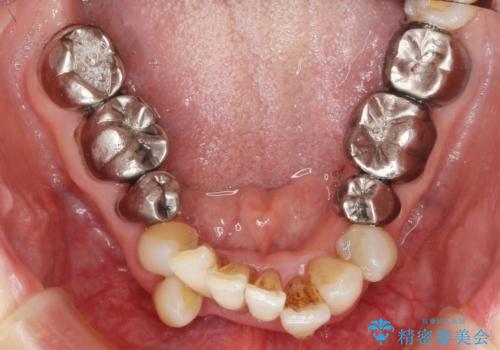

- 上顎前歯の黒ずみの改善、下顎前歯の十度なガタつき、矯正治療とセラミック治療を含む全体的な治療を希望され来院されました。

銀歯を高強度の仮歯に替えたのち、下顎前歯のみの部分矯正→全体的なマウスピース矯正治療(インビザライン)→最終的なセラミック治療と治療を進めます。